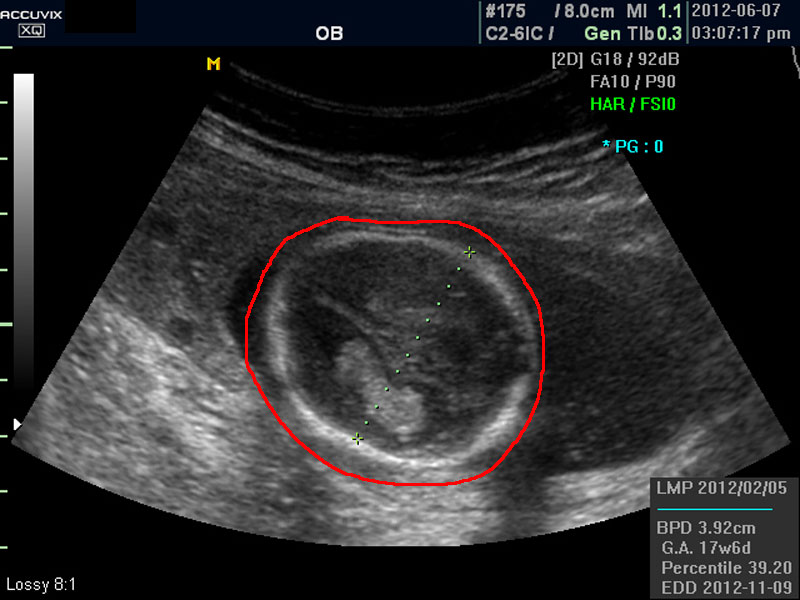

화면에서 좌측이 태아 머리 부분으로 빨간 펜으로 표시되어 있습니다.

위 사진에서 빨간 동그라미로 표시한 부분이 태아의 머리를 위에서 내려다 본 수평 단면입니다.

하얗게 보이는 것은 뼈이고 내부에 검게 보이는 것은 뇌실에 고인 척수액 부분이며 내부의 하얀 부분은 뇌조직과 뇌실 내 맥락막이라고 하는 것입니다.

모든 사진에서 우측 하단에는 기본적인 발육 정보가 기록되는데 세번째 사진에서 빨간 펜으로 표시한 부분이며 그 내용의 의미는 아래와 같습니다.

참고로 이런 측정 수치가 나타나는 양식이나 위치는 초음파 장비마다 다르지만 용어는 대체로 공통된 의학 용어를 사용하기 때문에 대동소이합니다.

1. LMP

Last Menstrual Period의 약자로 최종 월경일입니다. 이런 최종 월경일을 바탕으로 현재의 임신 주수와 초음파상 측정 지표들간에 얼마나 괴리 되어 있나 하는 것을 판단하는 것입니다.

3. GA

Gestational Age의 약자로 우리말로는 임신 주기라고 하며 CRL이나 BPD등을 기준으로 했을때 임신 몇주 며칠에 해당하는 지 나타낸 것입니다.

4. BPD

Biparietal Diameter의 약자로 머리를 위에서 보아서 양쪽 옆통수에서 반대쪽 옆통수까지의 길이입니다.

이는 임신 중기부터 후기까지 태아의 발육을 판단하는 중요한 지표이며 태아의 체중을 예측하는 데 쓰이는 지표 중 하나입니다.

5.EDD

Estimated Due Date의 약자로 초음파 측정치를 바탕으로 산출한 출산 예정일입니다.